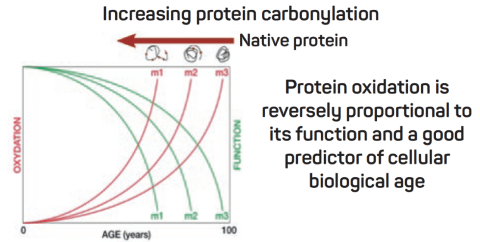

Protein carbonylation is detected and quantified with 2D-oxyDIGE, a novel proteomic approach using specific fluorescent cyanine dyes coupled with hydrazide probes which will react with protein carbonyls.

SOD-1 protein, an antioxidant protein, will be used to measure carbonylation. A panel of different mutations of the SOD-1 protein involved in ALS disease (amyotrophic lateral sclerosis) will be studied and assessed for their susceptibility to carbonylation and to form aggregates.

In order to improve the specificity and the sensitivity of the technique, nanocluster probes are under development to replace theses cy-hydrazide dyes.